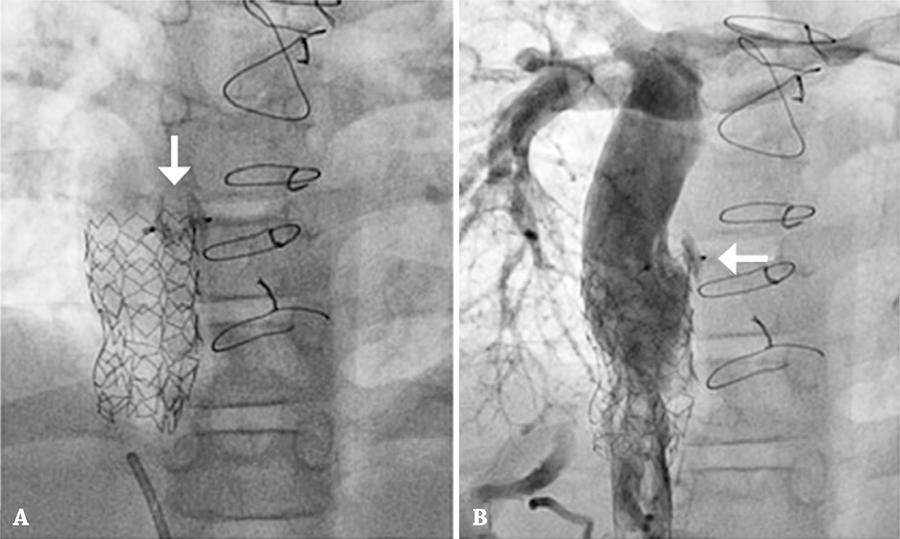

Figura 4

Oclusão da fenestração. (A) Amplatzer Duct Occluder II 5×6mm (AGA Medical Corporation) (seta). (B) Angiografia de controle demonstrando ausência de fluxo no local da prótese (seta).